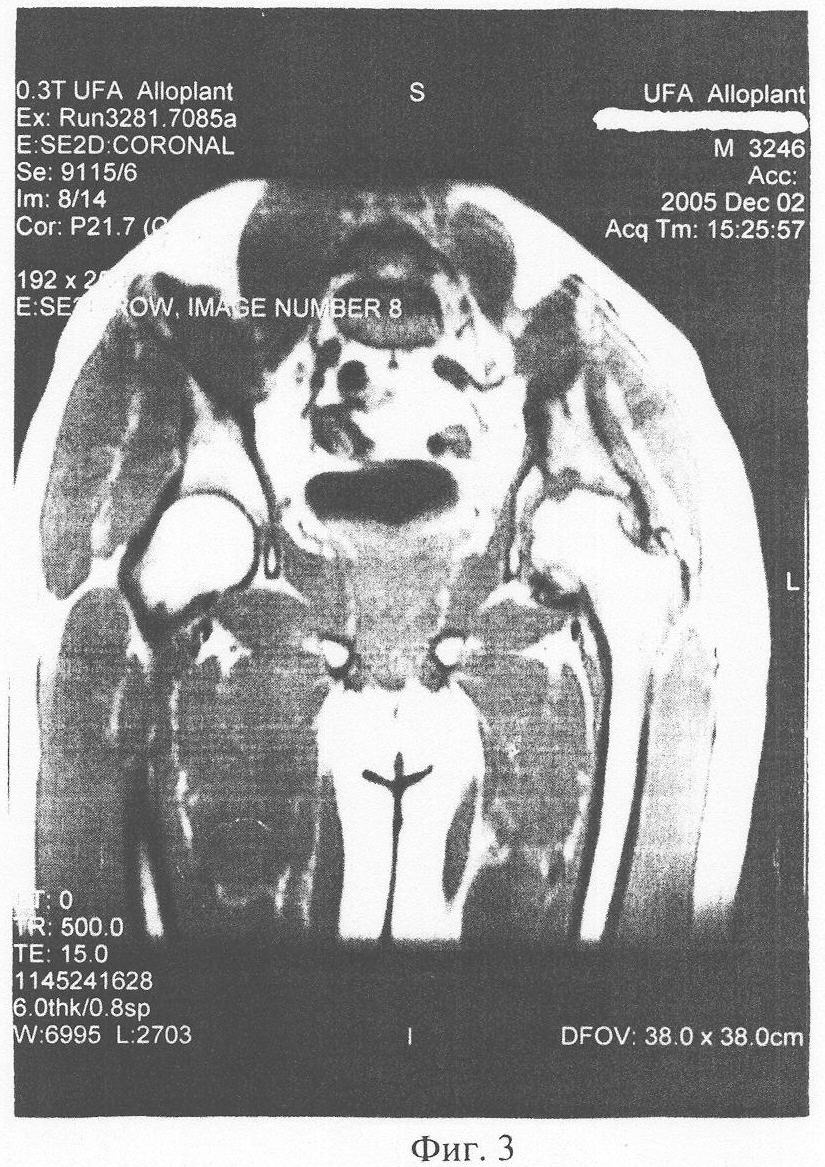

Очередной курс лечения был проведен в октябре 2005. В декабре ЯМР-томография (фиг.3): динамика положительная – появление ткани гидрофильной плотности, что свидетельствует о восстановлении питания хрящевой ткани и ее регенерации. Осевая нагрузка с применением костыля, в последующем – трости. В марте 2006 г, июле 2006 г проведены плановые очередные курсы введения ДБМА. ЯМР контроль в августе 2006 г (фиг.4) – появление конгруентности суставных поверхностей. Клинически: ходьба пациента свободная, без трости, движения в суставе в полном объеме, при осевой нагрузке болей нет.